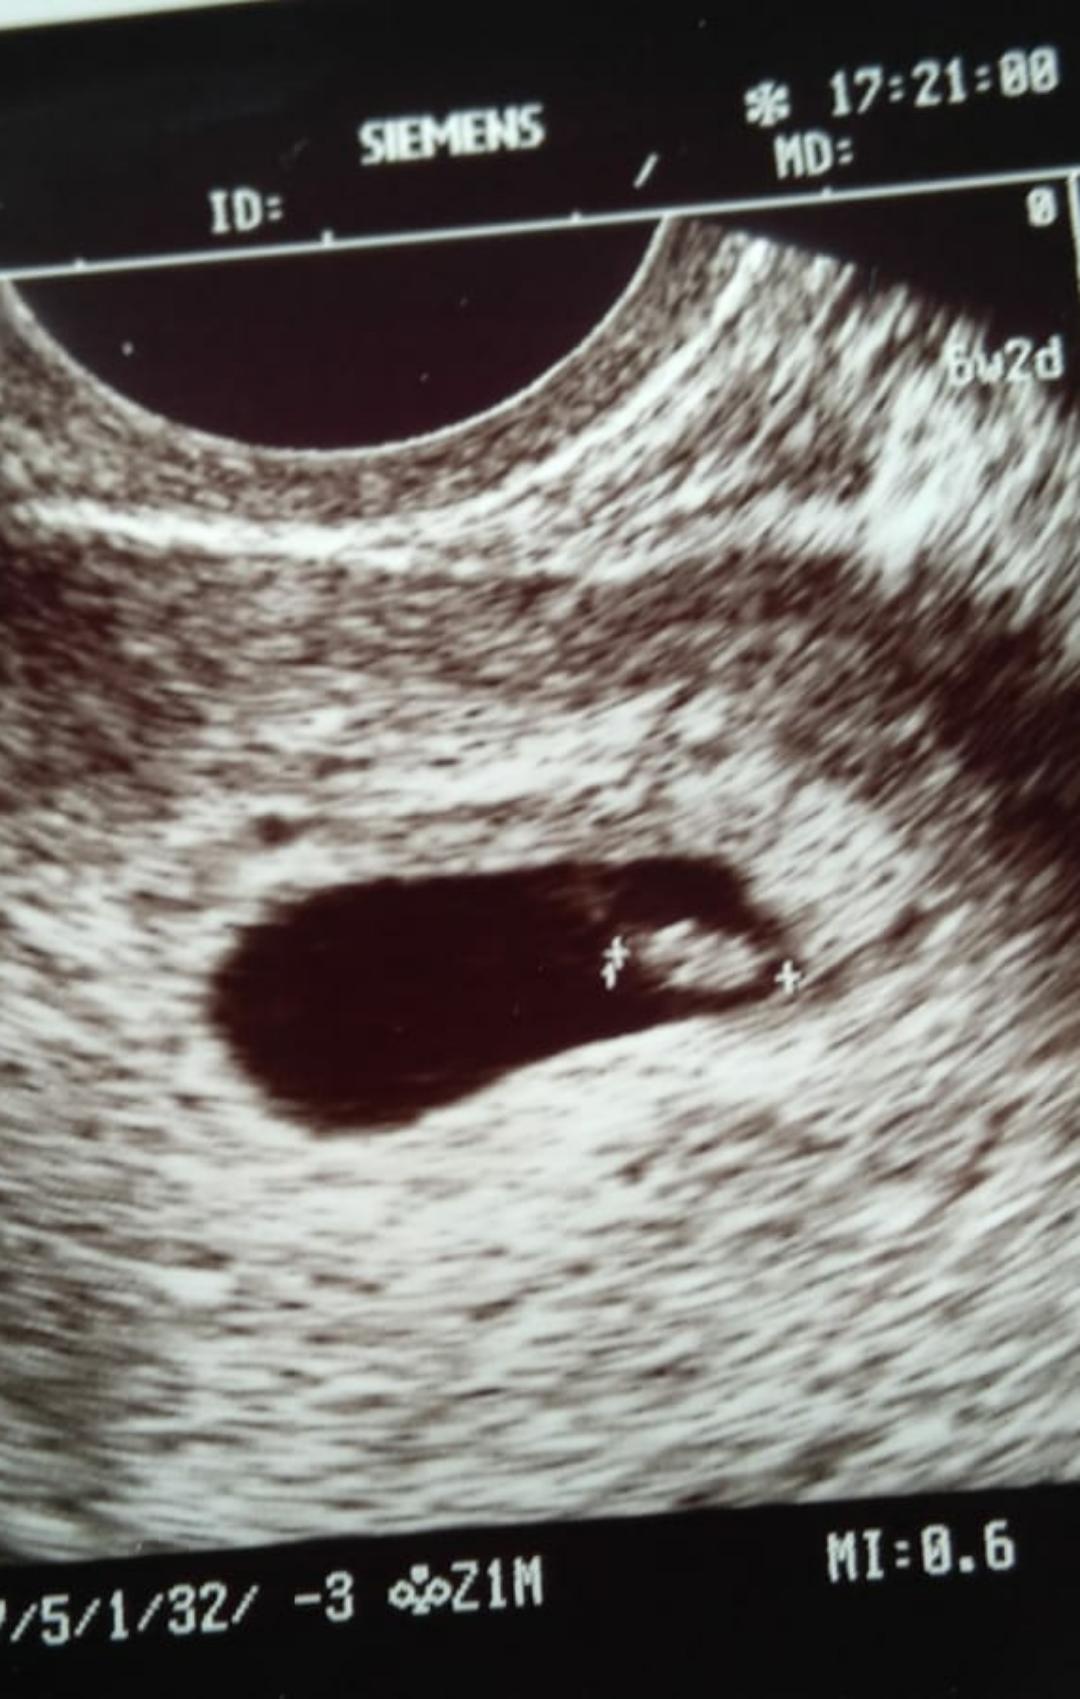

Witam! Byłam wczoraj u lekarza. Jestem w 6tyg jest to możliwe że jest już wszystko widać na usg i dostałam już kartę ciąży ?

Załączniki

• 8ec06da5a2fd0810d64cac3673dca1e9.jpg

8ec06da5a2fd0810d64cac3673dca1e9.jpg

148 KB · Wyświetleń: 103